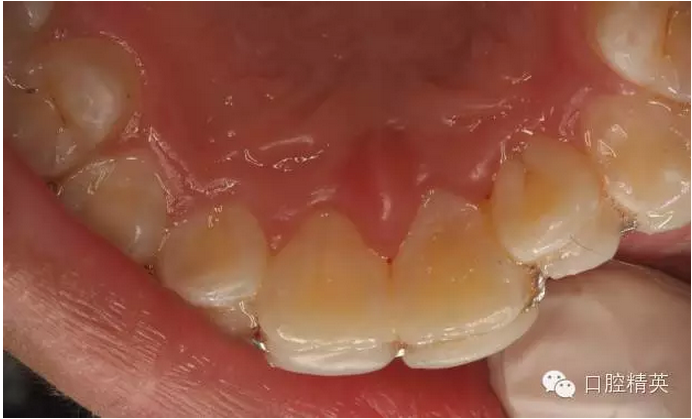

圖4.脫落的21離體牙,根面污染嚴(yán)重

圖5.體外21開(kāi)髓